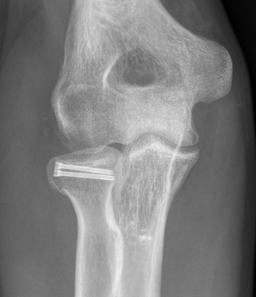

Overstuffing

| Lesser sigmoid notch | Symmetry of ulnohumeral joint |

|---|---|

|

Radial head shoulder articulate with lesser notch

Ensure no gapping of lateral ulnohumeral joint |

- cadaveric study

- increased medial ulno-humeral joint line gapping with overlengthening of 6 or 8 mm

- increased lateral ulno-humeral joint line gapping with overlengthening of 2 mm